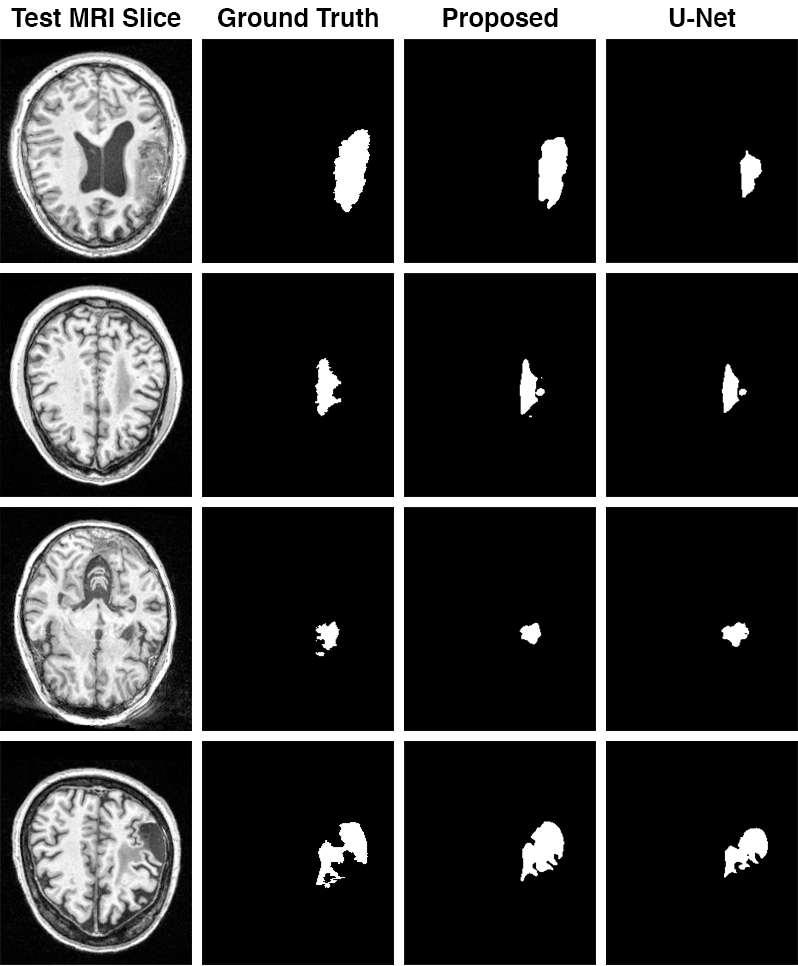

Some of the tested images from the ATLAS dataset are shown in Figure 7. State-of-the-art performance is not the goal of this work as the intention is to model the network follows the visual cortex anatomy so as to demonstrate the neuroscience intuition. Still, the proposed model can perform comparably to the de-facto standard U-Net Table 1.

Refer to caption

Figure 7: Segmentation examples on the ATLAS dataset